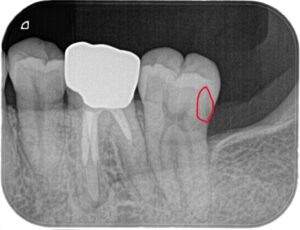

X線撮影を行いました。

あまりはっきりと映らなかったため、赤丸で囲んでみました。

神経付近まで虫歯は進行しています。